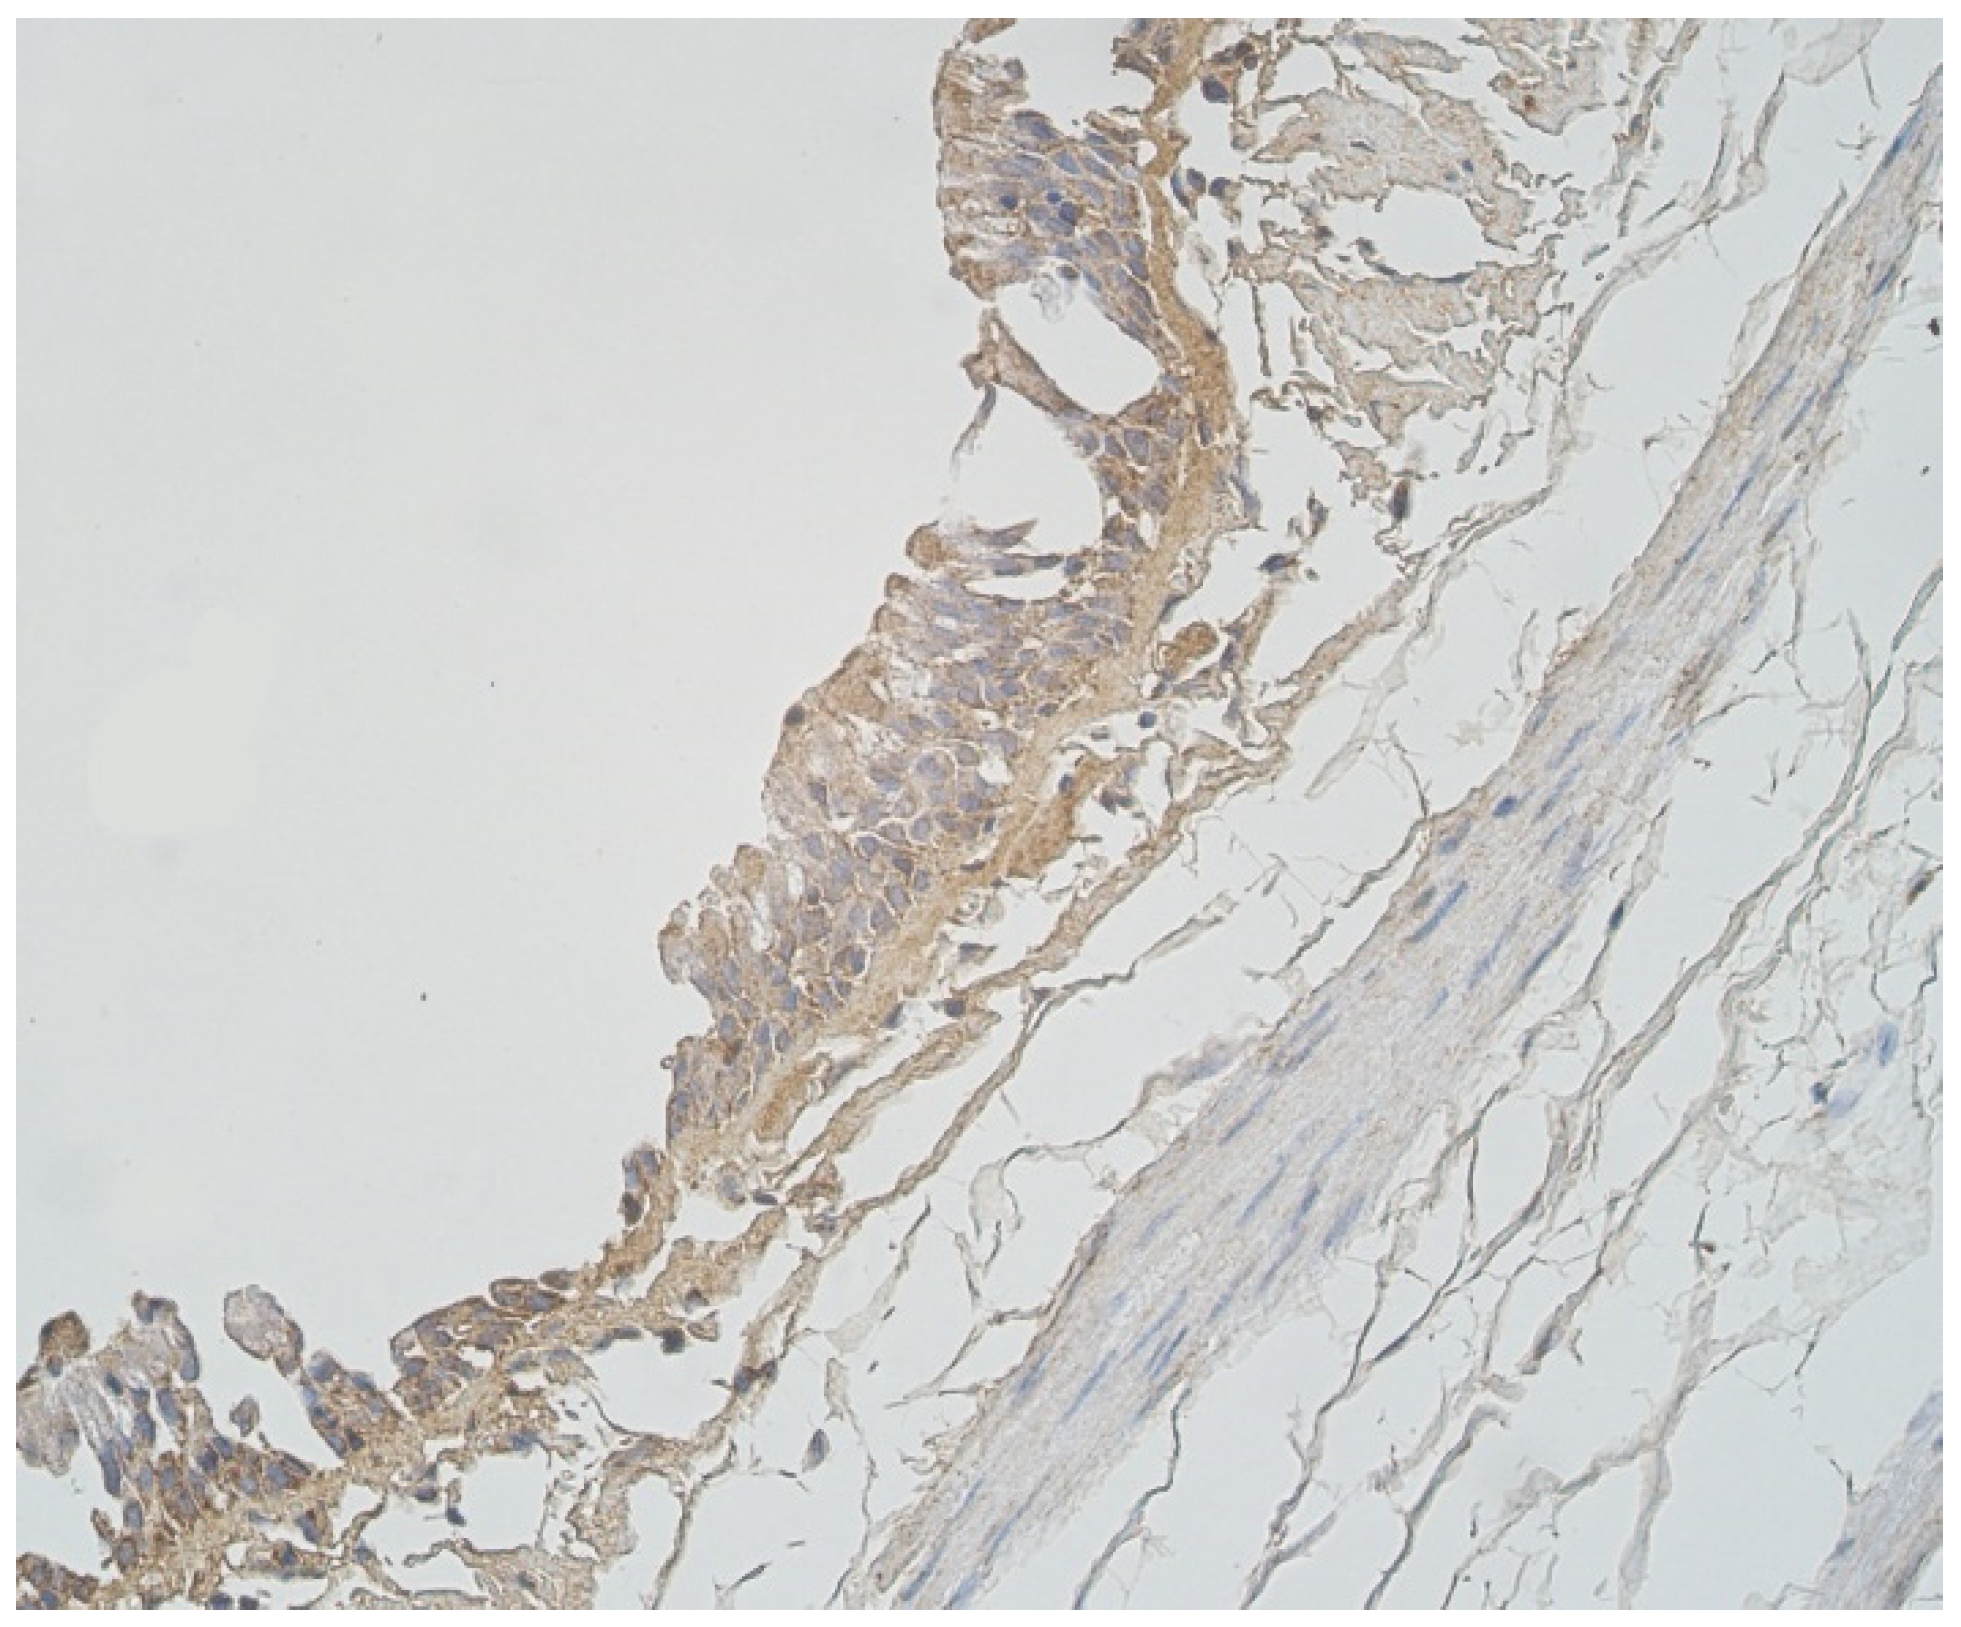

3.1. Tissue Review

3.2. Immunohistochemical (IMH) Data